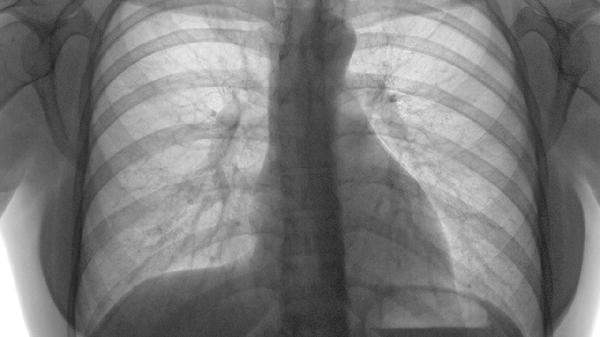

肺结节患者可在医生指导下使用盐酸左氧氟沙星片、头孢呋辛酯片、利福平胶囊、异烟肼片、复方甘草酸苷片等药物。肺结节可能与感染、结核、自身免疫性疾病等因素有关,需根据具体病因选用药物。

盐酸左氧氟沙星片适用于细菌感染引起的肺结节,属于喹诺酮类抗生素。该药物能通过抑制细菌DNA旋转酶发挥抗菌作用,对肺炎链球菌、流感嗜血杆菌等常见呼吸道病原体有较好效果。使用期间可能产生恶心、头晕等不良反应,须避免与含铝镁的抗酸剂同服。用药期间应定期复查胸部影像学评估疗效。

肺结节患者日常需保持居所通风良好,避免接触粉尘和二手烟。建议每日进行适度有氧运动如散步、太极拳,增强肺功能。饮食宜清淡富含优质蛋白,可适量食用银耳、百合等润肺食材,限制辛辣刺激性食物。严格遵医嘱用药并定期复查胸部CT,若出现咯血、持续胸痛等症状应及时就医。注意作息规律,保证充足睡眠,避免过度疲劳诱发症状加重。